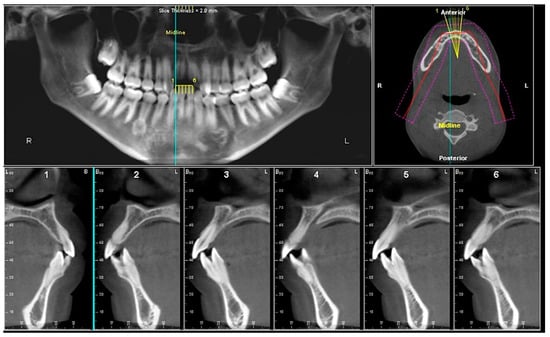

- Assessment of proposed sites of temporary anchorage device (TAD). Figure 11, Figure 12, Figure 13 and Figure 14 show correction of the Class II molar relationship using a temporary anchorage device. Figure 11 shows a pre-treatment intraoral photograph of the right side. The Class II molar relationship can be observed. Figure 12 shows coronal, sagittal and axial views, as well as a volume rendering of CBCT that was acquired in order to assess the site of the temporary anchorage device. Figure 13 shows an intraoral photograph of the right side, in which the TAD was placed mesial to the maxillary first molar, and a power chain was attached from this TAD to a hook placed distal to the lateral incisor. Figure 14 shows a post-treatment intraoral photograph showing improvement of the Class II molar relationship after removal of all orthodontic appliances.